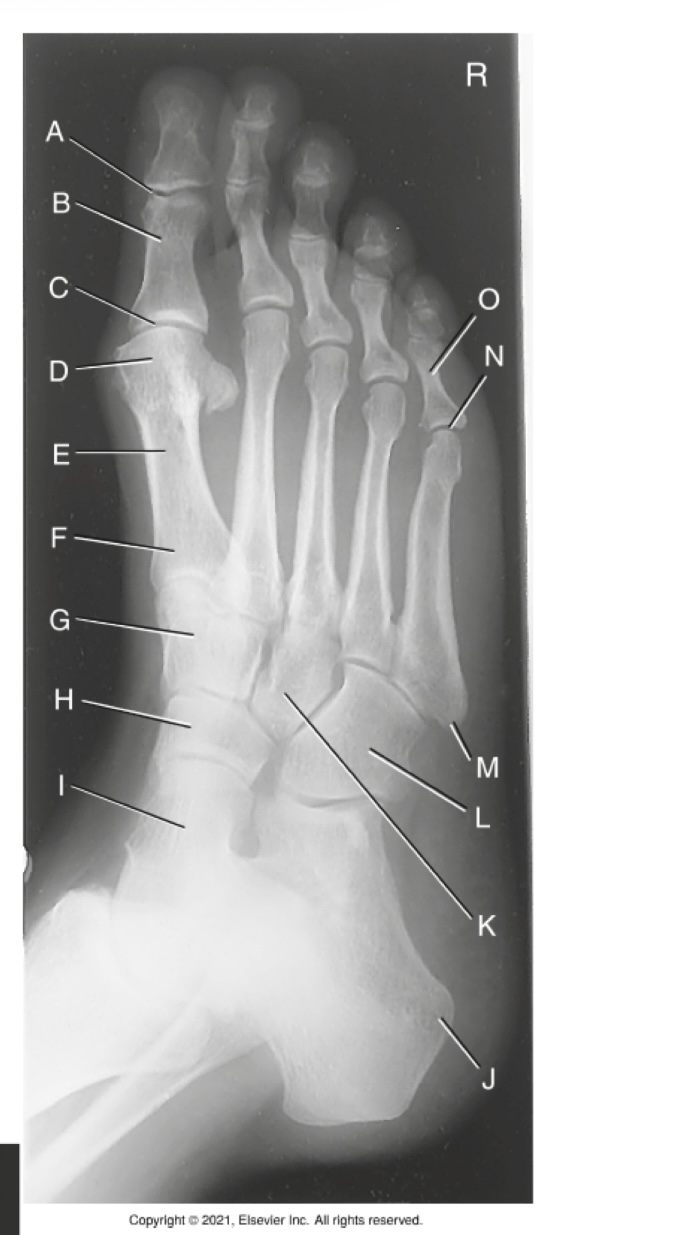

(AP AXIAL FOOT) what is A?

First metatarsophalangealjoint

what is B?

First tarsometatarsal joint

what is C?

Medial cuneiform

what is D?

Navicular

A

Interphalangeal joint of 1st digit

B

Proximal phalanx of 1st digit

C

Metatarsophalangeal joint of 1st digit (MTP joint)

D

Head of 1st metatarsal

E

Body of 1st metatarsal

F

Base of 1st metatarsal

G

Second/ intermediate cuneiform

H

I

Talus

J

Tuberosity of calcaneus

K

Third / lateral cuneiform